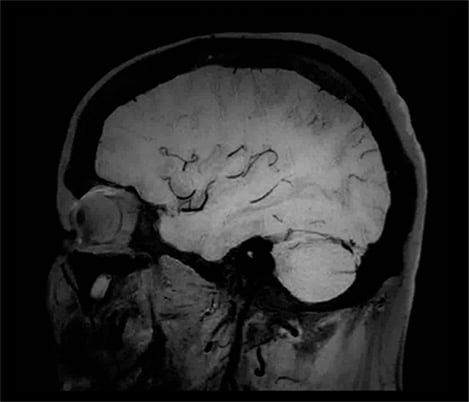

Casos clínicos de casi todas las anatomías Explore más de 100 casos clínicos de sus colegas en todo el mundo que muestran cómo la tecnología digital de resonancia magnética de Philips fortalece sus necesidades de imágenes.